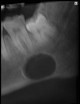

: DEFECTO OSEO DE STAFNE